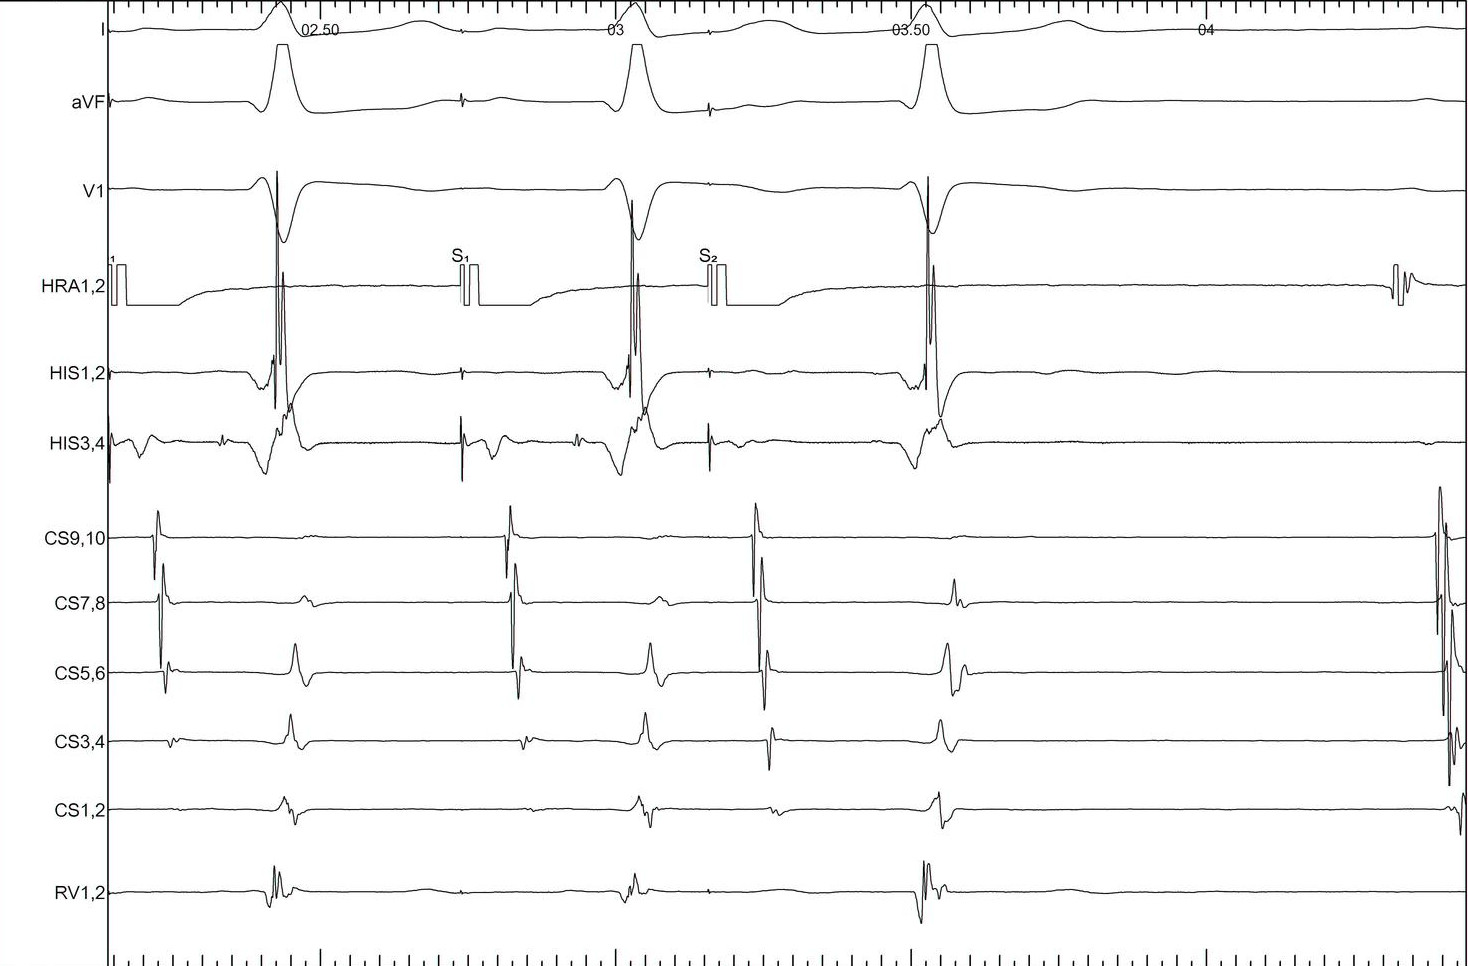

His refractory PVC - setting up

• R synchronised single extrastimuli

• Check that sync is working

• Start 30 ms less than RR

• Decrement by 10 ms

• Continue until refractoriness or tachycardia termination

His refractory PVC - measurement and interpretation

• Confirm cycle length is stable

• Measure AA around each PVC to find longest CI at which PVC preexcites A

• Decide if His is refractory at this time

PVC during tachycardia

his_pvc.jpg

PVC terminates tachycardia

his_ref_pvc.jpg